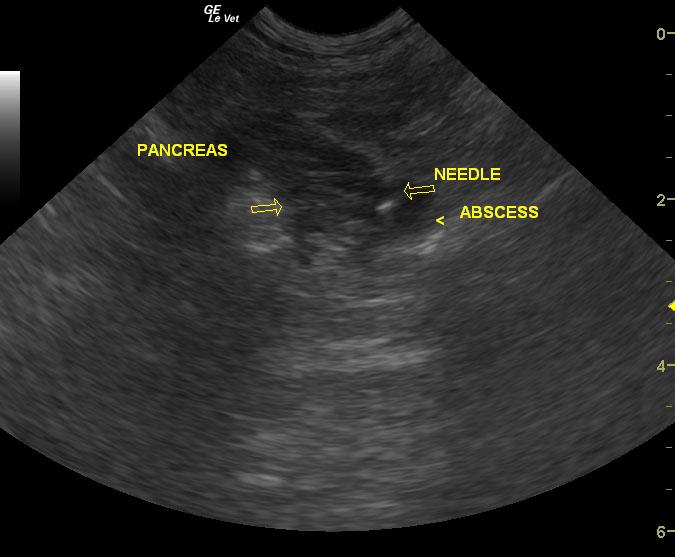

Extensive mixed hypoechoic pancreatic parenchyma is noted much of which lacks blood flow on power Doppler assessment. Gastroduodenal thickening is noted with duodenal spasm. Cavitations are noted in the pancreas with echogenic fluid. Extensive hyperechoic fat is noted.

Sampling

FNA revealed necrosis.